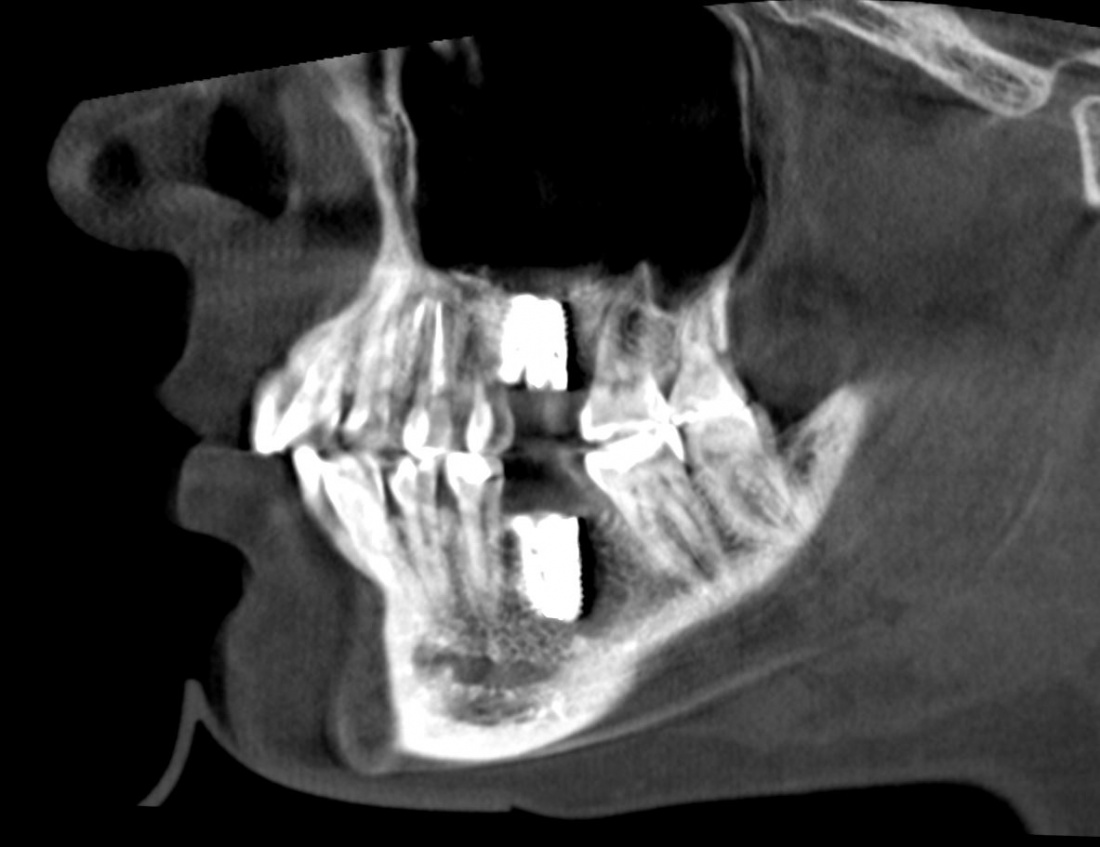

В общем, так и получилось. Уж не помню, почему я наобещал пациентке, что мы поставим ей имплантаты одновременно с остеопластикой. Но я наобещал. И, когда увидел клиническую картину в полости рта:

у меня появились серьезные сомнения, смогу ли я выполнить своё обещание. Вот только не спрашивай меня «Вот чо, сложно было по КЛКТ посмотреть?». Я же не спрашиваю тебя, где ты был в 2013 году, и сделал ли ты домашку. Но, в целом, план операции у нас не поменялся. Как и было оговорено, мы проведем остеопластику с одновременной имплантацией в боковом участке нижней челюсти справа.

Кстати, обрати внимание на ширину альвеолярного гребня (левая картинка). Она чуть меньше 3 мм. Это объясняет, почему я засомневался в возможности установки имплантатов одновременно с остеопластикой. Понятно и без КЛКТ.

Возвращаемся к основной операционной области. Еще раз посмотрим на альвеолярный гребень, поофигеваем от его ширины и моих грандиозных планов: